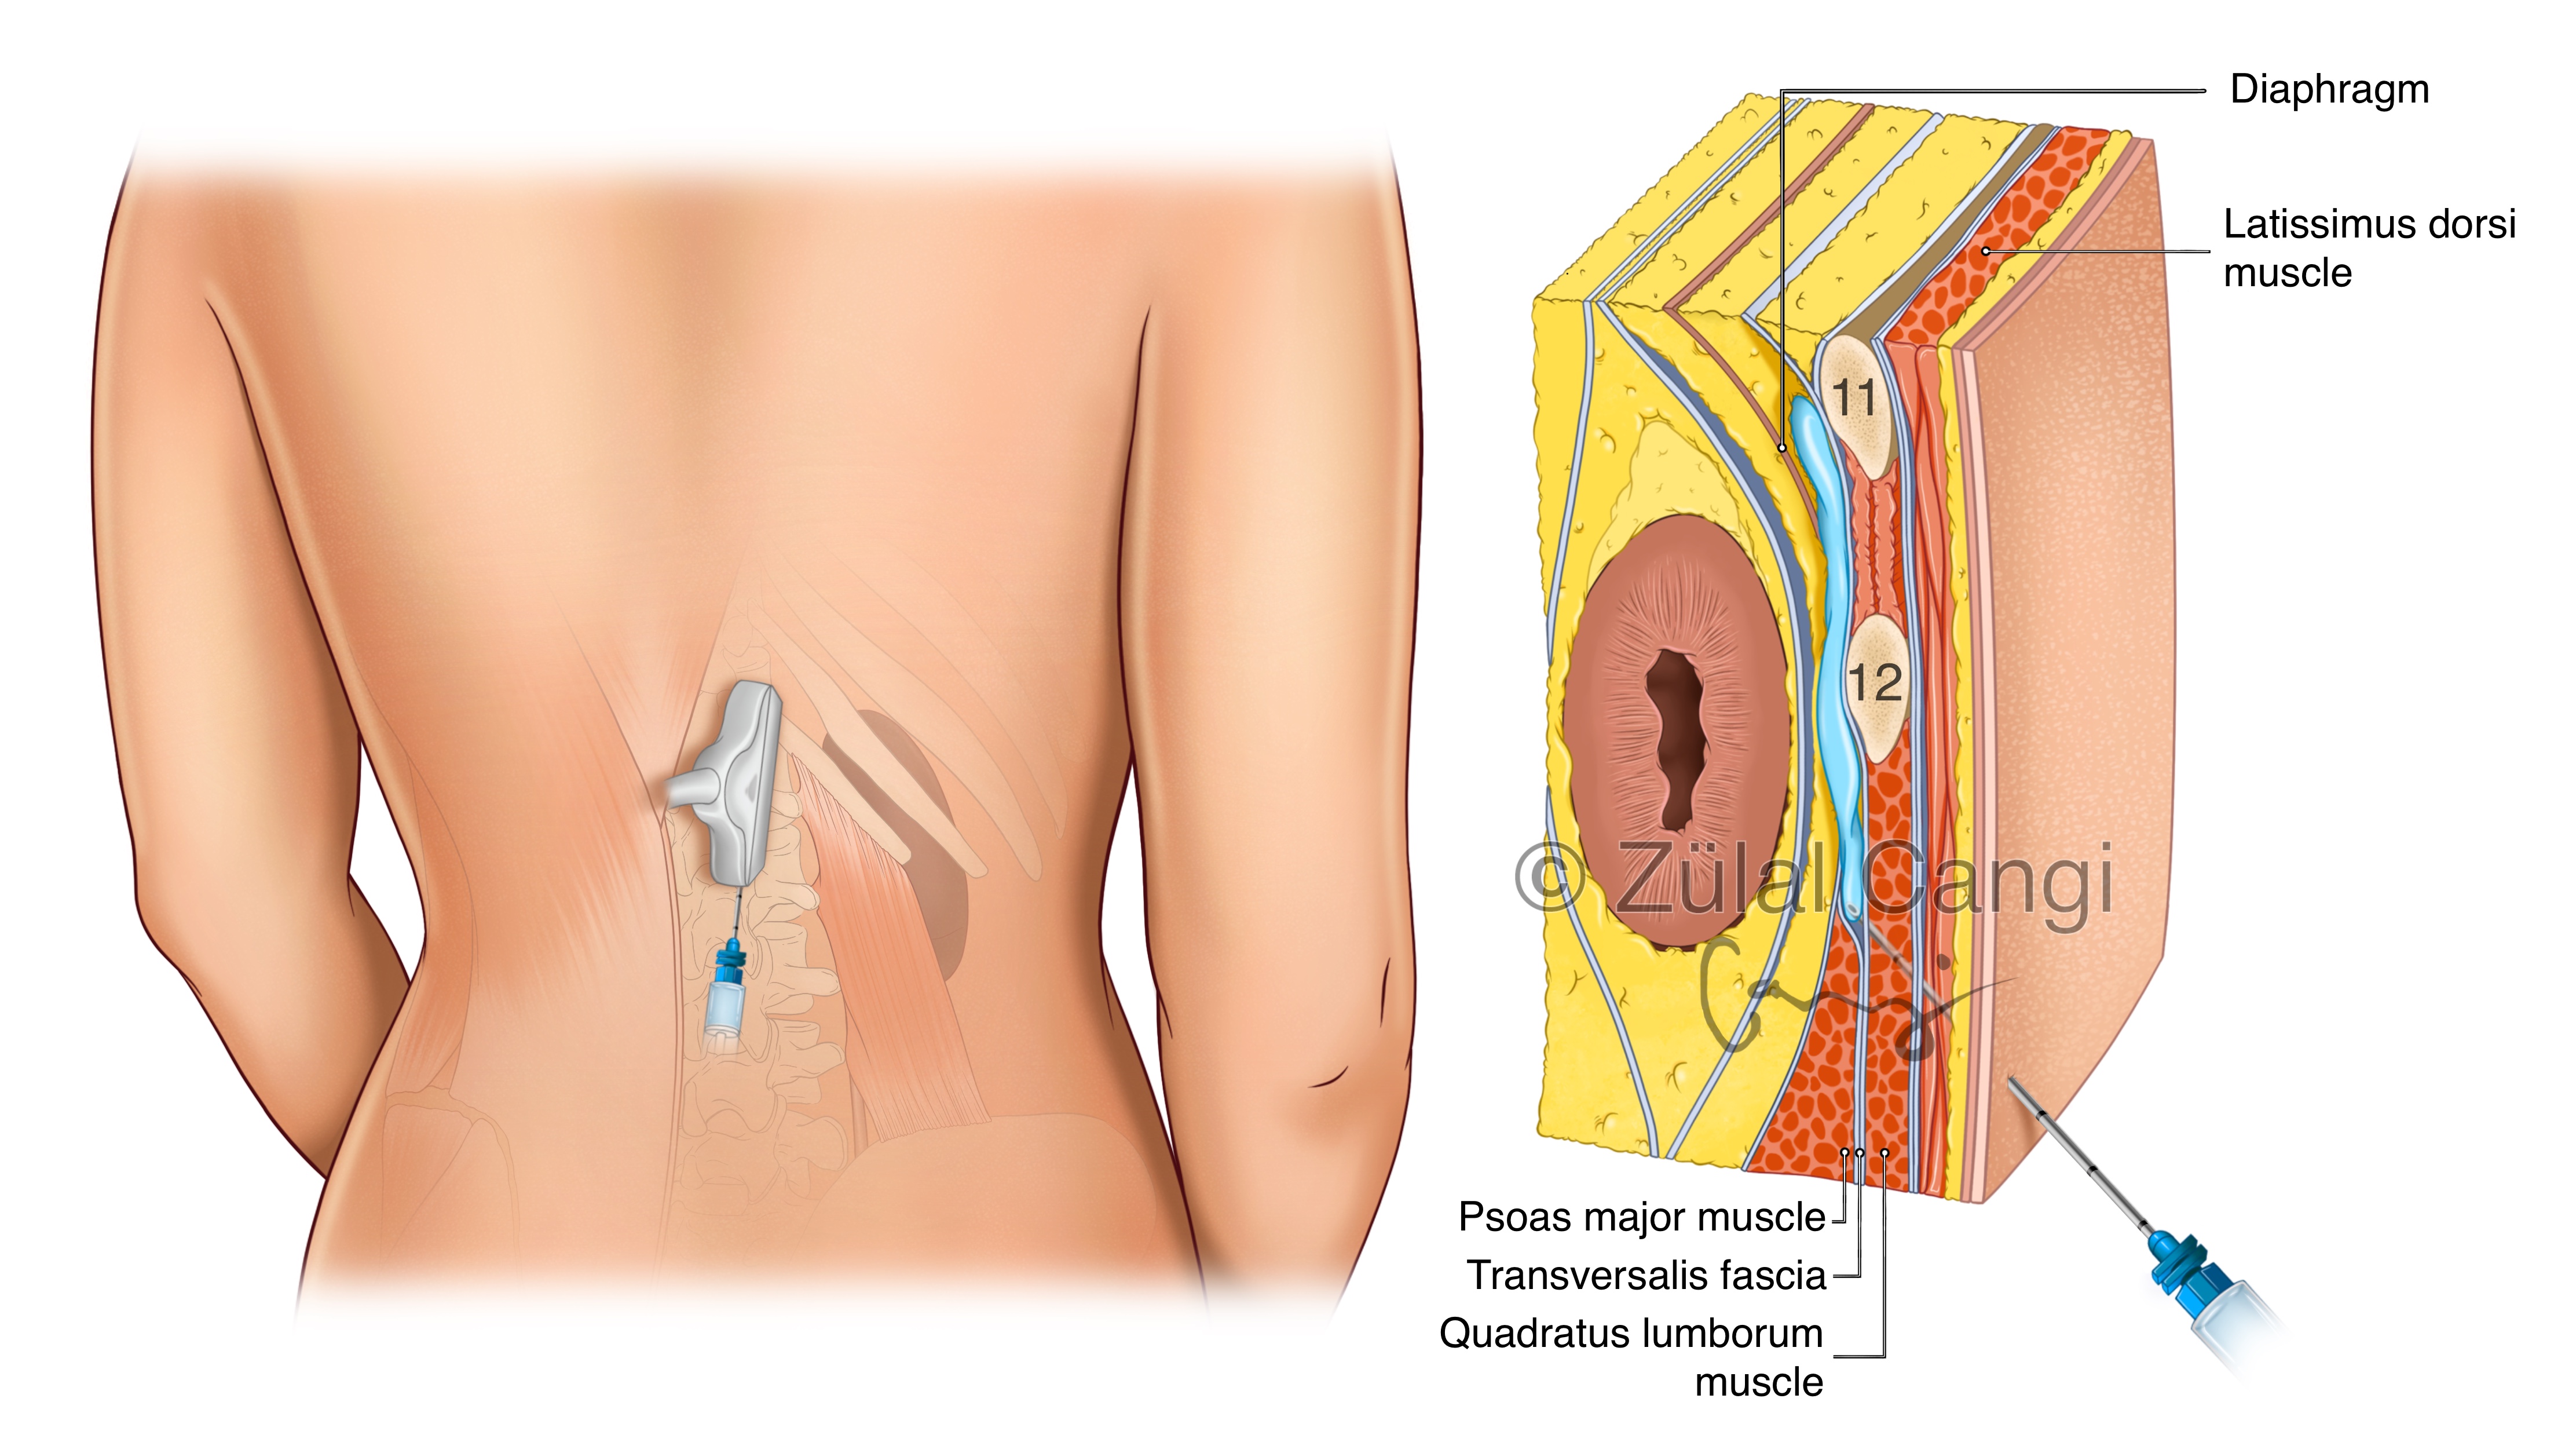

Sanatın estetiğini bilimin kesinliğiyle bir araya getiren Zülal Cangi, medikal ve bilimsel illüstrasyon alanındaki çalışmalarıyla akademik yayınlar, eğitim materyalleri ve çeşitli bilimsel platformlar için görsel içerikler üretmektedir. Amacı, bilimsel bilgiyi yalnızca doğru biçimde aktarmakla kalmayıp, aynı zamanda öğretici ve estetik bir dille görünür kılmaktır.

PORTFÖY